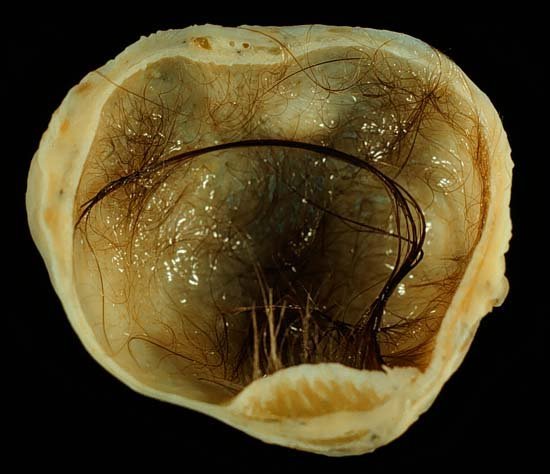

คนไข้รายนี้ มาด้วยอาการประจำเดือนมาไม่สม่ำเสมอ, มีเลือดออกจากช่องคลอดระหว่างรอบเดือน, ปวดหน่วงในอุ้งเชิงกรานเรื้อรังหรือเป็นๆหายๆ ปวดมากขึ้นในช่วงก่อนมีประจำเดือน มีปวดร้าวไปที่หลังบางครั้ง

แพทย์ Ultra sound พบก้อนขนาดใหญ่มาก เป็นมา ๑ ปีแต่กว่าจะได้ผ่าตัด ไม่มีเลือด ต้องรอเลือดอยู่หลายเดือน คนไข้ปฏิเสธที่จะไปผ่าตัดที่รพ.มหาราช นม จะขอผ่าตัดที่สูงเนินเท่านั้น.. แฟนพันธ์แท้ของคุณหมอชาติชัย ดวงดีเด่น (สูติแพทย์ของเรา)

ซีสต์มีหลายอย่าง แต่ที่เห็นในภาพเรียก Dermoid Cyst เป็นซีสต์ที่ผิดปกติ เกิดขึ้นในหญิงอายุน้อย เส้นผ่านศูนย์กลางโตได้ถึง 6 นิ้ว ซีสต์ประเภทนี้จะมีส่วนประกอบคล้ายเซลล์ผิวหนังอยู่ด้านใน เช่นเส้นผม ขน ฟัน กระดูก ลูกตา

ซีสต์ (Cyst) หมายถึง ถุงน้ำ หรือก้อนตุ่มไตที่ผิดปกติ มักเป็นเนื้องอกไม่ร้าย (ไม่เป็นมะเร็ง) ประเภทหนึ่ง มีลักษณะเป็นถุงเมมเบรนปิดแยกออกจากเนื้อเยื่อบริเวณใกล้เคียง ภายในอาจบรรจุอากาศ ของเหลว ไขมัน หรือเซลล์ผิวหนัง เช่น กระดูก ฟัน ลูกตา เล็บ หรือเส้นผมเป็นต้น

ซีสต์ เกิดขึ้นได้ในหลายๆตำแหน่งภายในร่างกาย ที่พบบ่อย เช่น ที่บริเวณเต้านม เปลือกตา รังไข่ นิ้วมือ แขน ขา ไต และใต้ผิวหนังส่วนต่างๆ ซีสต์มีหลายชนิด เรียกแตกต่างกันตามลักษณะการเกิด ตำแหน่งที่เกิด และลักษณะของซีสต์เอง เช่น เดอร์มอยด์ซีสต์ (Dermoid cyst หรือ Teratoma) เกิดจากเซลล์ผิวหนังที่จัดวางอยู่ผิดตำแหน่งตั้งแต่พัฒนาการขั้นแรกของทารกในครรภ์ มักพบเส้นผม เล็บ กระดูก ไขมันอยู่ภายใน